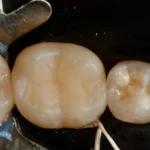

Confira este caso clínico de restauração dentária posterior, terceiro molar, com a resina tipo Bulk da 3M.

Passo a passo de como remover restauração de amálgama